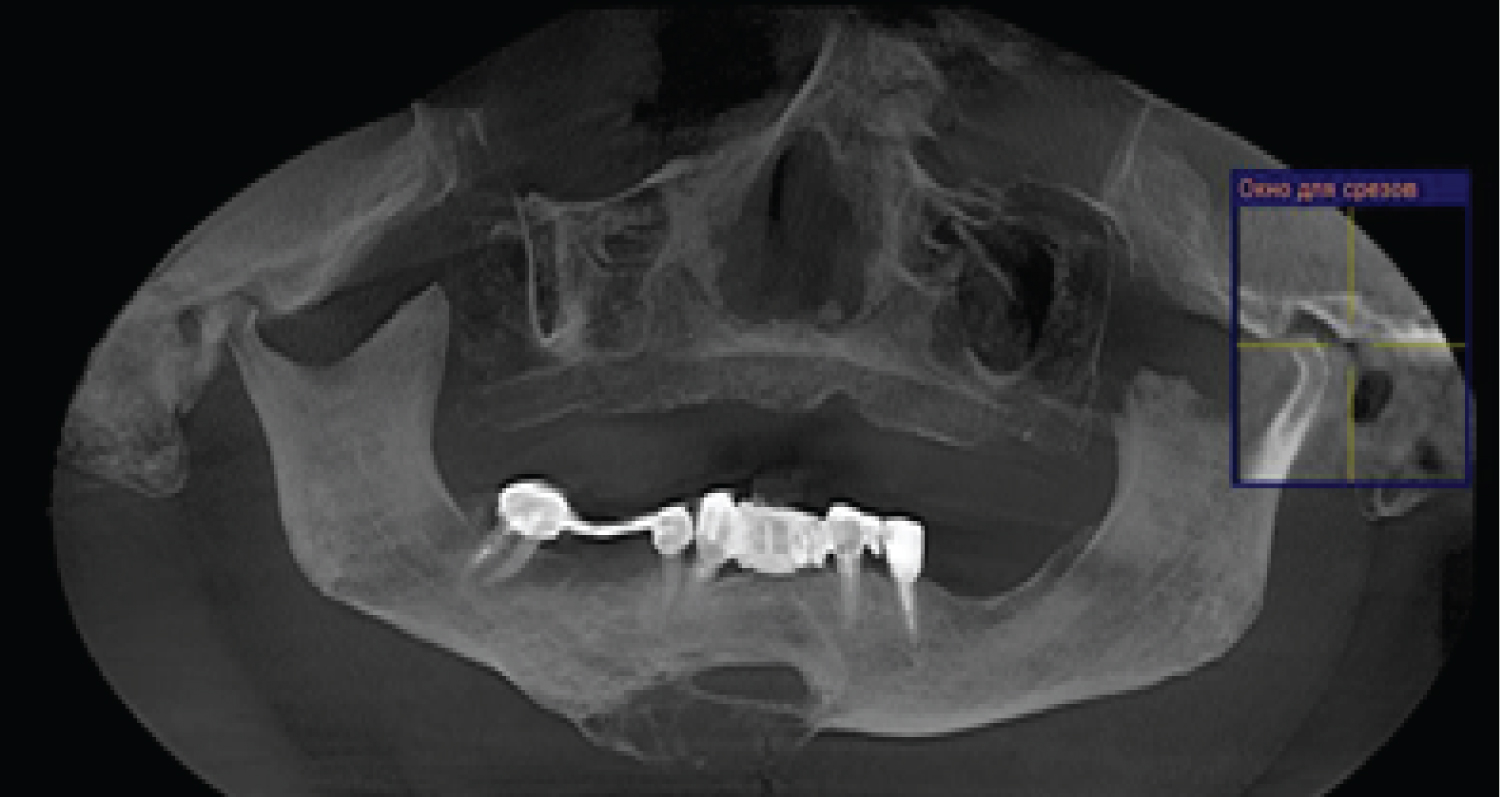

To assess the degree of osseointegration and determine the timing of the functional load of dental implants installed in free vascularized bone autografts, a Resonance-Frequency Analysis (RFA) of the stability of implants using Osstell Mentor (Osstell instrument, Integration Diagnostics AB, Gothenburg, Sweden) at time of implant placement, after 3 months. All patients presented functional and esthetic complaints. All patients underwent a thorough clinical laboratory, radiological examination according to a generally accepted scheme. Patients were evaluated by preoperative and postoperative outcome using computed tomography scan evaluation using CT Galileos (Sirona, German) (Figure 2, Figure 3, Figure 4, Figure 5 and Figure 6). Biopsy of the lesion was obtained in all cases. The choice of surgical treatment is determined by the type of lesions and the sizes of jaw defect.

Figure 2: (Patients 1) Preoperative CT scan showing Low differential osteosarcoma (stage T4N0 M0). View Figure 2